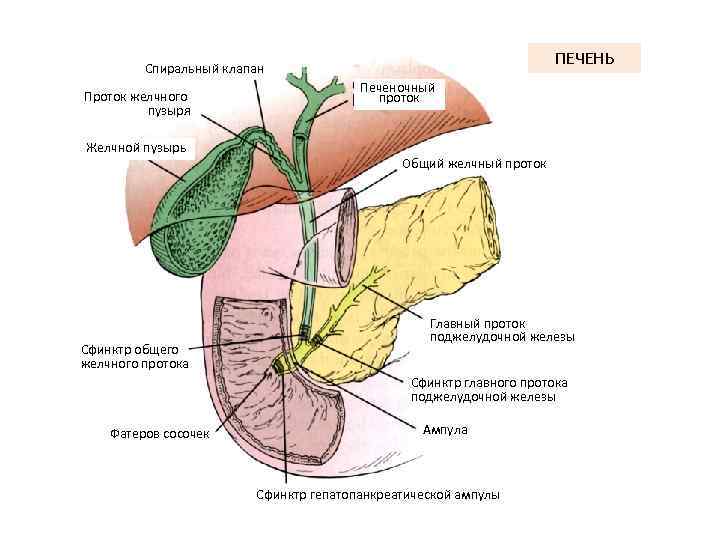

ПЕЧЕНЬ Спиральный клапан Проток желчного пузыря Желчной пузырь Сфинктр общего желчного протока Печеночный проток Общий желчный проток Главный проток поджелудочной железы Сфинктр главного протока поджелудочной железы Фатеров сосочек Ампула Сфинктр гепатопанкреатической ампулы